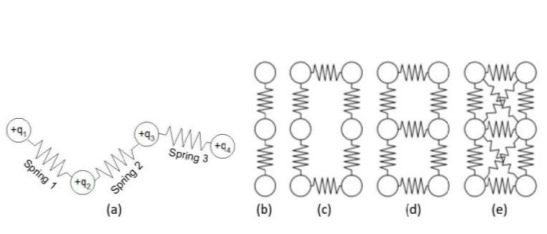

Tri menjelaskan bahwa metode SCPM ini termasuk ke dalam deformable model. Model ini memiliki kemampuan mengikuti kontur suatu objek yang diinginkan, menentukan batas region of interest (ROI), serta meningkatkan pemulihan bentuk. Ditambah dengan tingkat fleksibilitas yang baik tanpa perlu komputasi yang tinggi. Namun, SCPM ini akan kesulitan jika diterapkan pada gambar yang berkualitas rendah dan berantakan.

Guna mengatasi kekurangan ini, alumnus S1 Teknik Elektro ITS ini menyebutkan bahwa SCPM mengombinasikan partikel bermuatan positif dengan pegas. Partikel ini akan bergerak menuju kontur benda bermuatan negatif yang dihasilkan oleh citra biomedis. “Kombinasi pegas ini akan mencegah partikel bergerak saling menjauh dan menjaganya agar berada di jarak yang sesuai tanpa mengurangi fleksibilitasnya,” jelas Tri.

Selanjutnya, SCPM sendiri sudah diuji lewat kurva sederhana, dengan menunjukkan bentuk yang diberikan meskipun terdapat banyak noise. Selain itu, metode ini juga telah diujikan pada kurva terbuka dan tertutup dengan hasil yang baik. Bahkan pada pengujian kurva tertutup, kemampuan SCPM menunjukkan hasil bahwa SCPM lebih unggul dibandingkan dengan Charge Fluid Model dan Active Contour.

Susunan partikel SCPM yang merupakan kombinasi dari partikel bermuatan positif yang dihubungkan dengan pegas